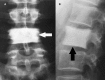

Signs of Nature in Spine Radiology

As medical science developed over time, we have relied on natural imagery to help us recognise and remember things. In this review article, we will be discussing some radiological signs named because of their resemblance to the occurrences in the natural world.

- Codfish vertebra sign. Amin OSM. https://s3.amazonaws.com/academia.edu.documents/51980839/cod-fish_verteb... BMJ Case Rep. 2017 - PMC - PubMed